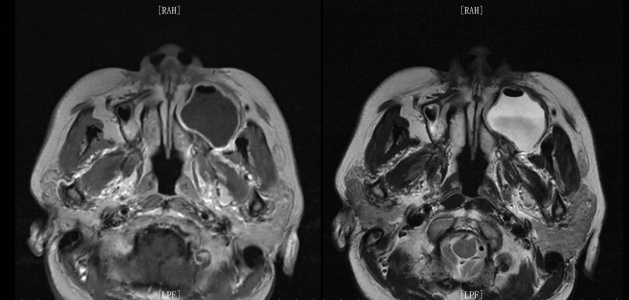

术前影像学检查:MRI检查及CT检查示左侧上颌骨内囊肿样病变,直径约4.0厘米,周围骨质呈压迫性吸收,左侧上颌窦腔被压迫缩小。